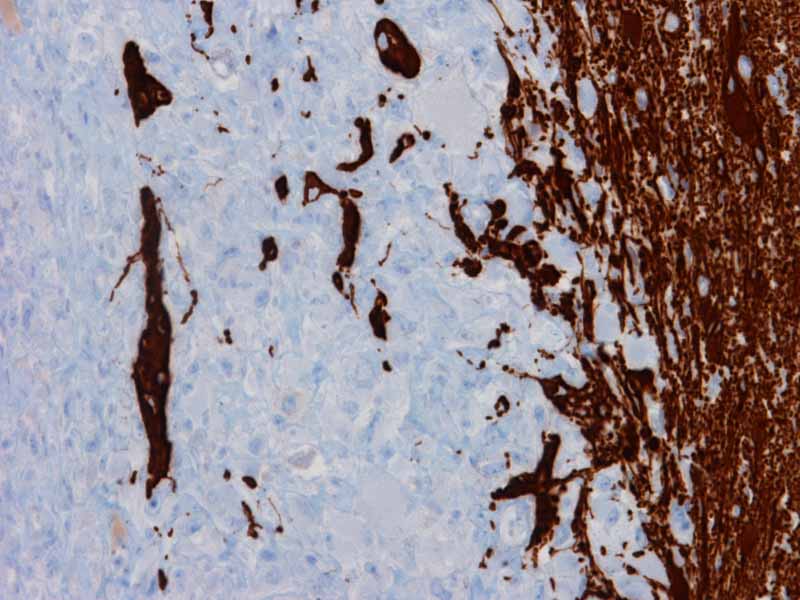

Glail fibrillary acidic protein (GFAP)

Glial fibrillary acidic protein (GFAP): Focal but strong immunopositivity is present in this tumor.

Vimentin

Vimentin: Practically every cell is immunoreactive for vimentin. Note the belly of strongly positive cytoplasm in the tumor cells. This feature is rather characteristic for rhabdoid cells.